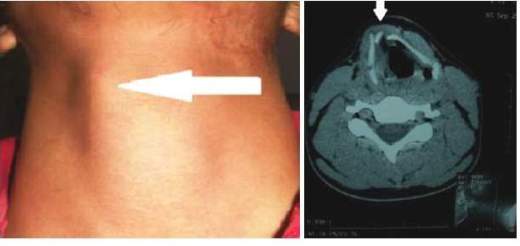

A 20-year-old male patient attended the emergency room after having a trauma on the neck. The physical examination revealed dysphonia and deviation of the cartilage thyroid to the right (figure 1). A direct laryngoscopy showed a small hematoma on the right side of the larynx with no active bleeding. A CT scan of the neck revealed fracture of the cartilage thyroid. Schaeffer EIII (displaced stable fracture). The patient was treated with steroids, antibiotics and observation for 24 hours not presenting respiratory distress. The patient was discharged to be followed monthly for one year, period in which he was asymptomatic and with no dysphonia.